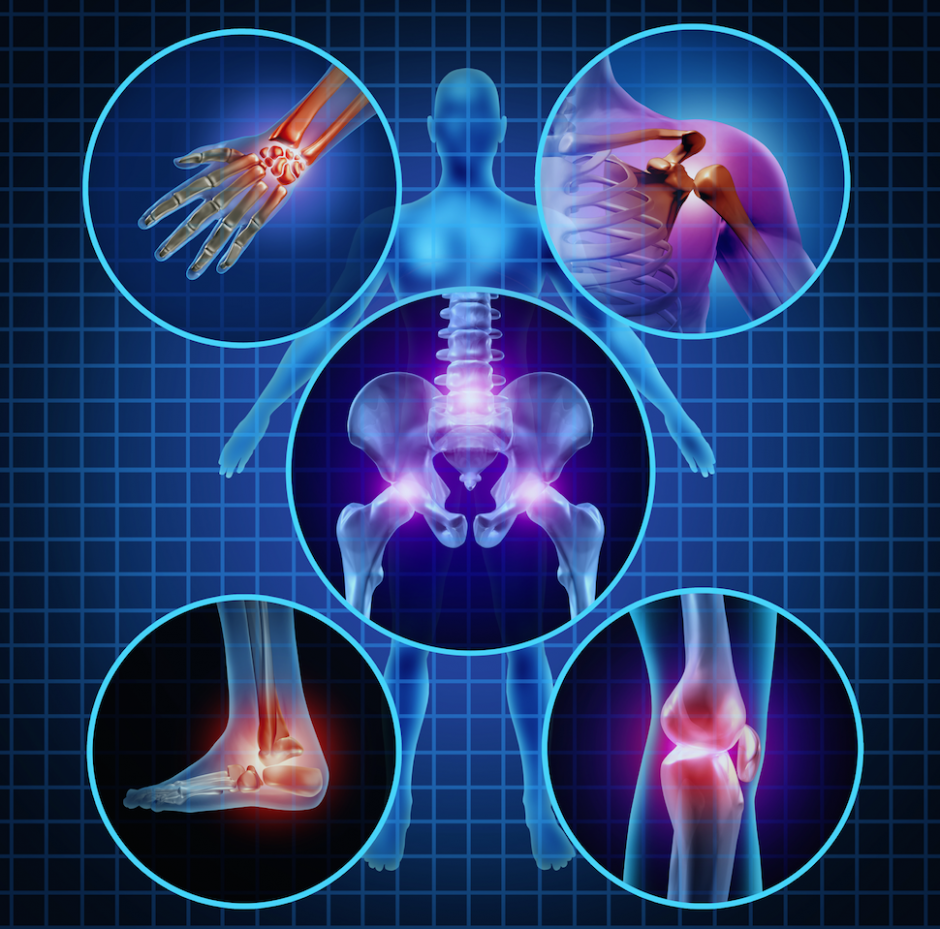

Osteoarthritis Is Disability . These changes usually develop slowly and. It is also one of the most common causes of physical disability among adults. It’s a leading cause of disability. Arthritis causes more than just pain. Under the americans with disabilities act (ada),. Osteoarthritis may be considered a disability if it significantly impacts a person’s ability to perform major life activities, including work. In recent years, we have gained important insights into the cause and pathogenesis of pain in osteoarthritis. Osteoarthritis is a degenerative joint disease that happens when the tissues that cushion the ends of the bones within the joints break down over time. A disability is a condition that limits your typical movements,. If your osteoarthritis is so hard to manage that leaving the workforce is a must, you may qualify for social security disability benefits. Osteoarthritis is the most common form of arthritis among older adults. With an ageing and increasingly obese population, this syndrome is becoming even more prevalent than in previous decades. Osteoarthritis is a leading cause of disability and source of societal cost in older adults. So, if your osteoarthritis severely limits your ability to walk, stand, or use your hands, you could be considered disabled under.

Osteoarthritis Is Disability With an ageing and increasingly obese population, this syndrome is becoming even more prevalent than in previous decades. If your osteoarthritis is so hard to manage that leaving the workforce is a must, you may qualify for social security disability benefits. Arthritis causes more than just pain. Osteoarthritis is a leading cause of disability and source of societal cost in older adults. Osteoarthritis is the most common form of arthritis among older adults. In recent years, we have gained important insights into the cause and pathogenesis of pain in osteoarthritis. These changes usually develop slowly and. So, if your osteoarthritis severely limits your ability to walk, stand, or use your hands, you could be considered disabled under. Osteoarthritis is a degenerative joint disease that happens when the tissues that cushion the ends of the bones within the joints break down over time. With an ageing and increasingly obese population, this syndrome is becoming even more prevalent than in previous decades. It’s a leading cause of disability. A disability is a condition that limits your typical movements,. It is also one of the most common causes of physical disability among adults. Under the americans with disabilities act (ada),. Osteoarthritis may be considered a disability if it significantly impacts a person’s ability to perform major life activities, including work.